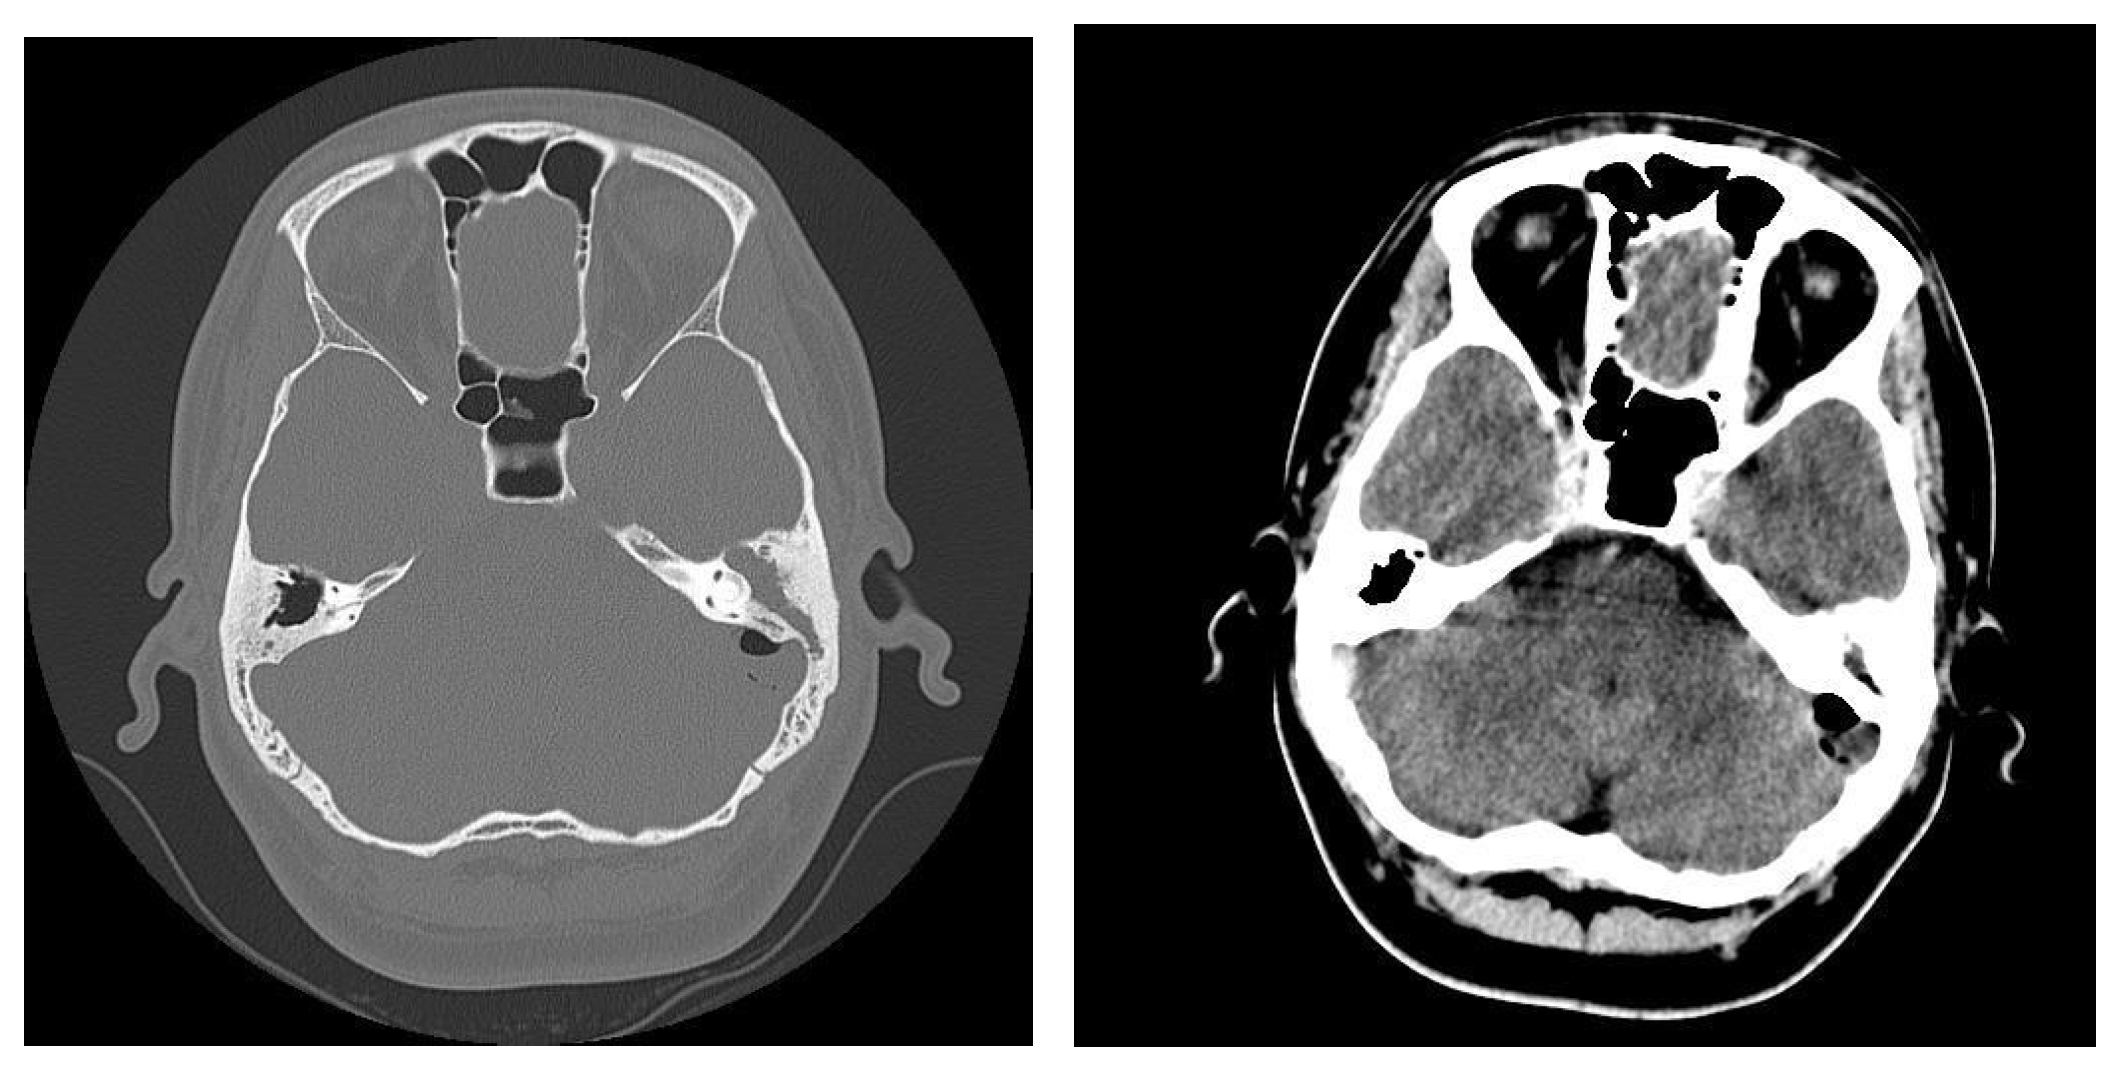

3.1.2. Computed Tomography and Magnetic Resonance Imaging

| CT Aspects | Number of Patients | Percentage |

|---|---|---|

| Fluid accumulation | 168 | 100% |

| Osteolysis | 152 | 90.47% |

| Osteocondensations | 128 | 76.19% |

| Cholesteatoma | 48 | 28.57% |

| Exocranial extensions | 48 | 28.57% |

| Intracranial extensions | 24 | 14.28% |

| Changes to the external auditory canal | 68 | 40.47% |

| Ossicular chain damage | 144 | 85.71% |